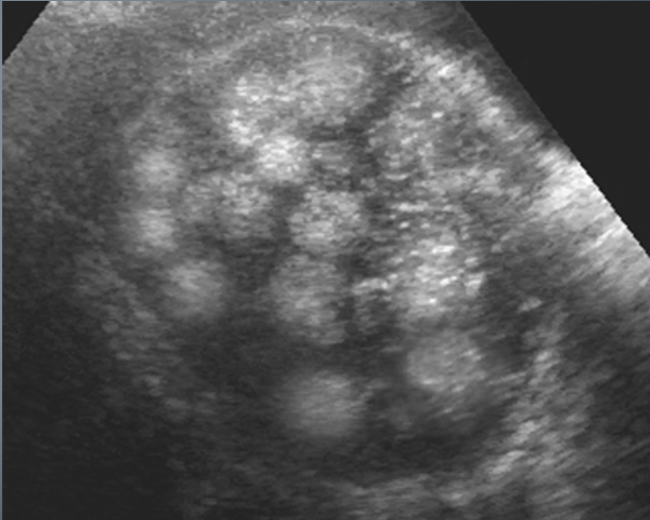

PCOS U/S appearance:

Bilateral enlargement

Contain multiple (12 or more), tiny peripheral cysts 2-9 mm

Ovarian volume >10 cm

25% of pt’s have normal appearing ovaries

The US appearance of PCOS may appear in women whose ovaries are treated with FSH

“String of Pearls” or “Black Pearl Necklace”